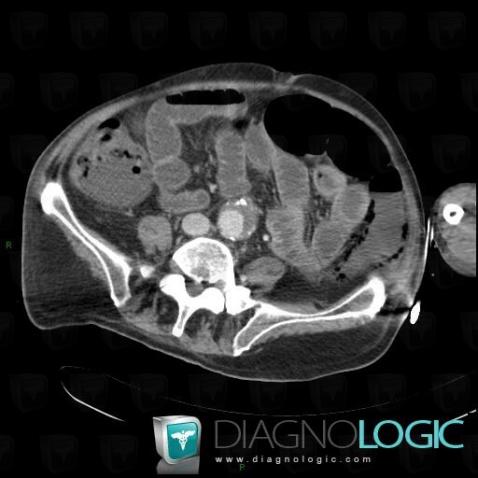

Portal venous gas, Portal vein and branches, CT

Here is the specific information in the key image above:

- Diagnosis Portal venous gas, Location(s) Portal vein and branches, with gamuts